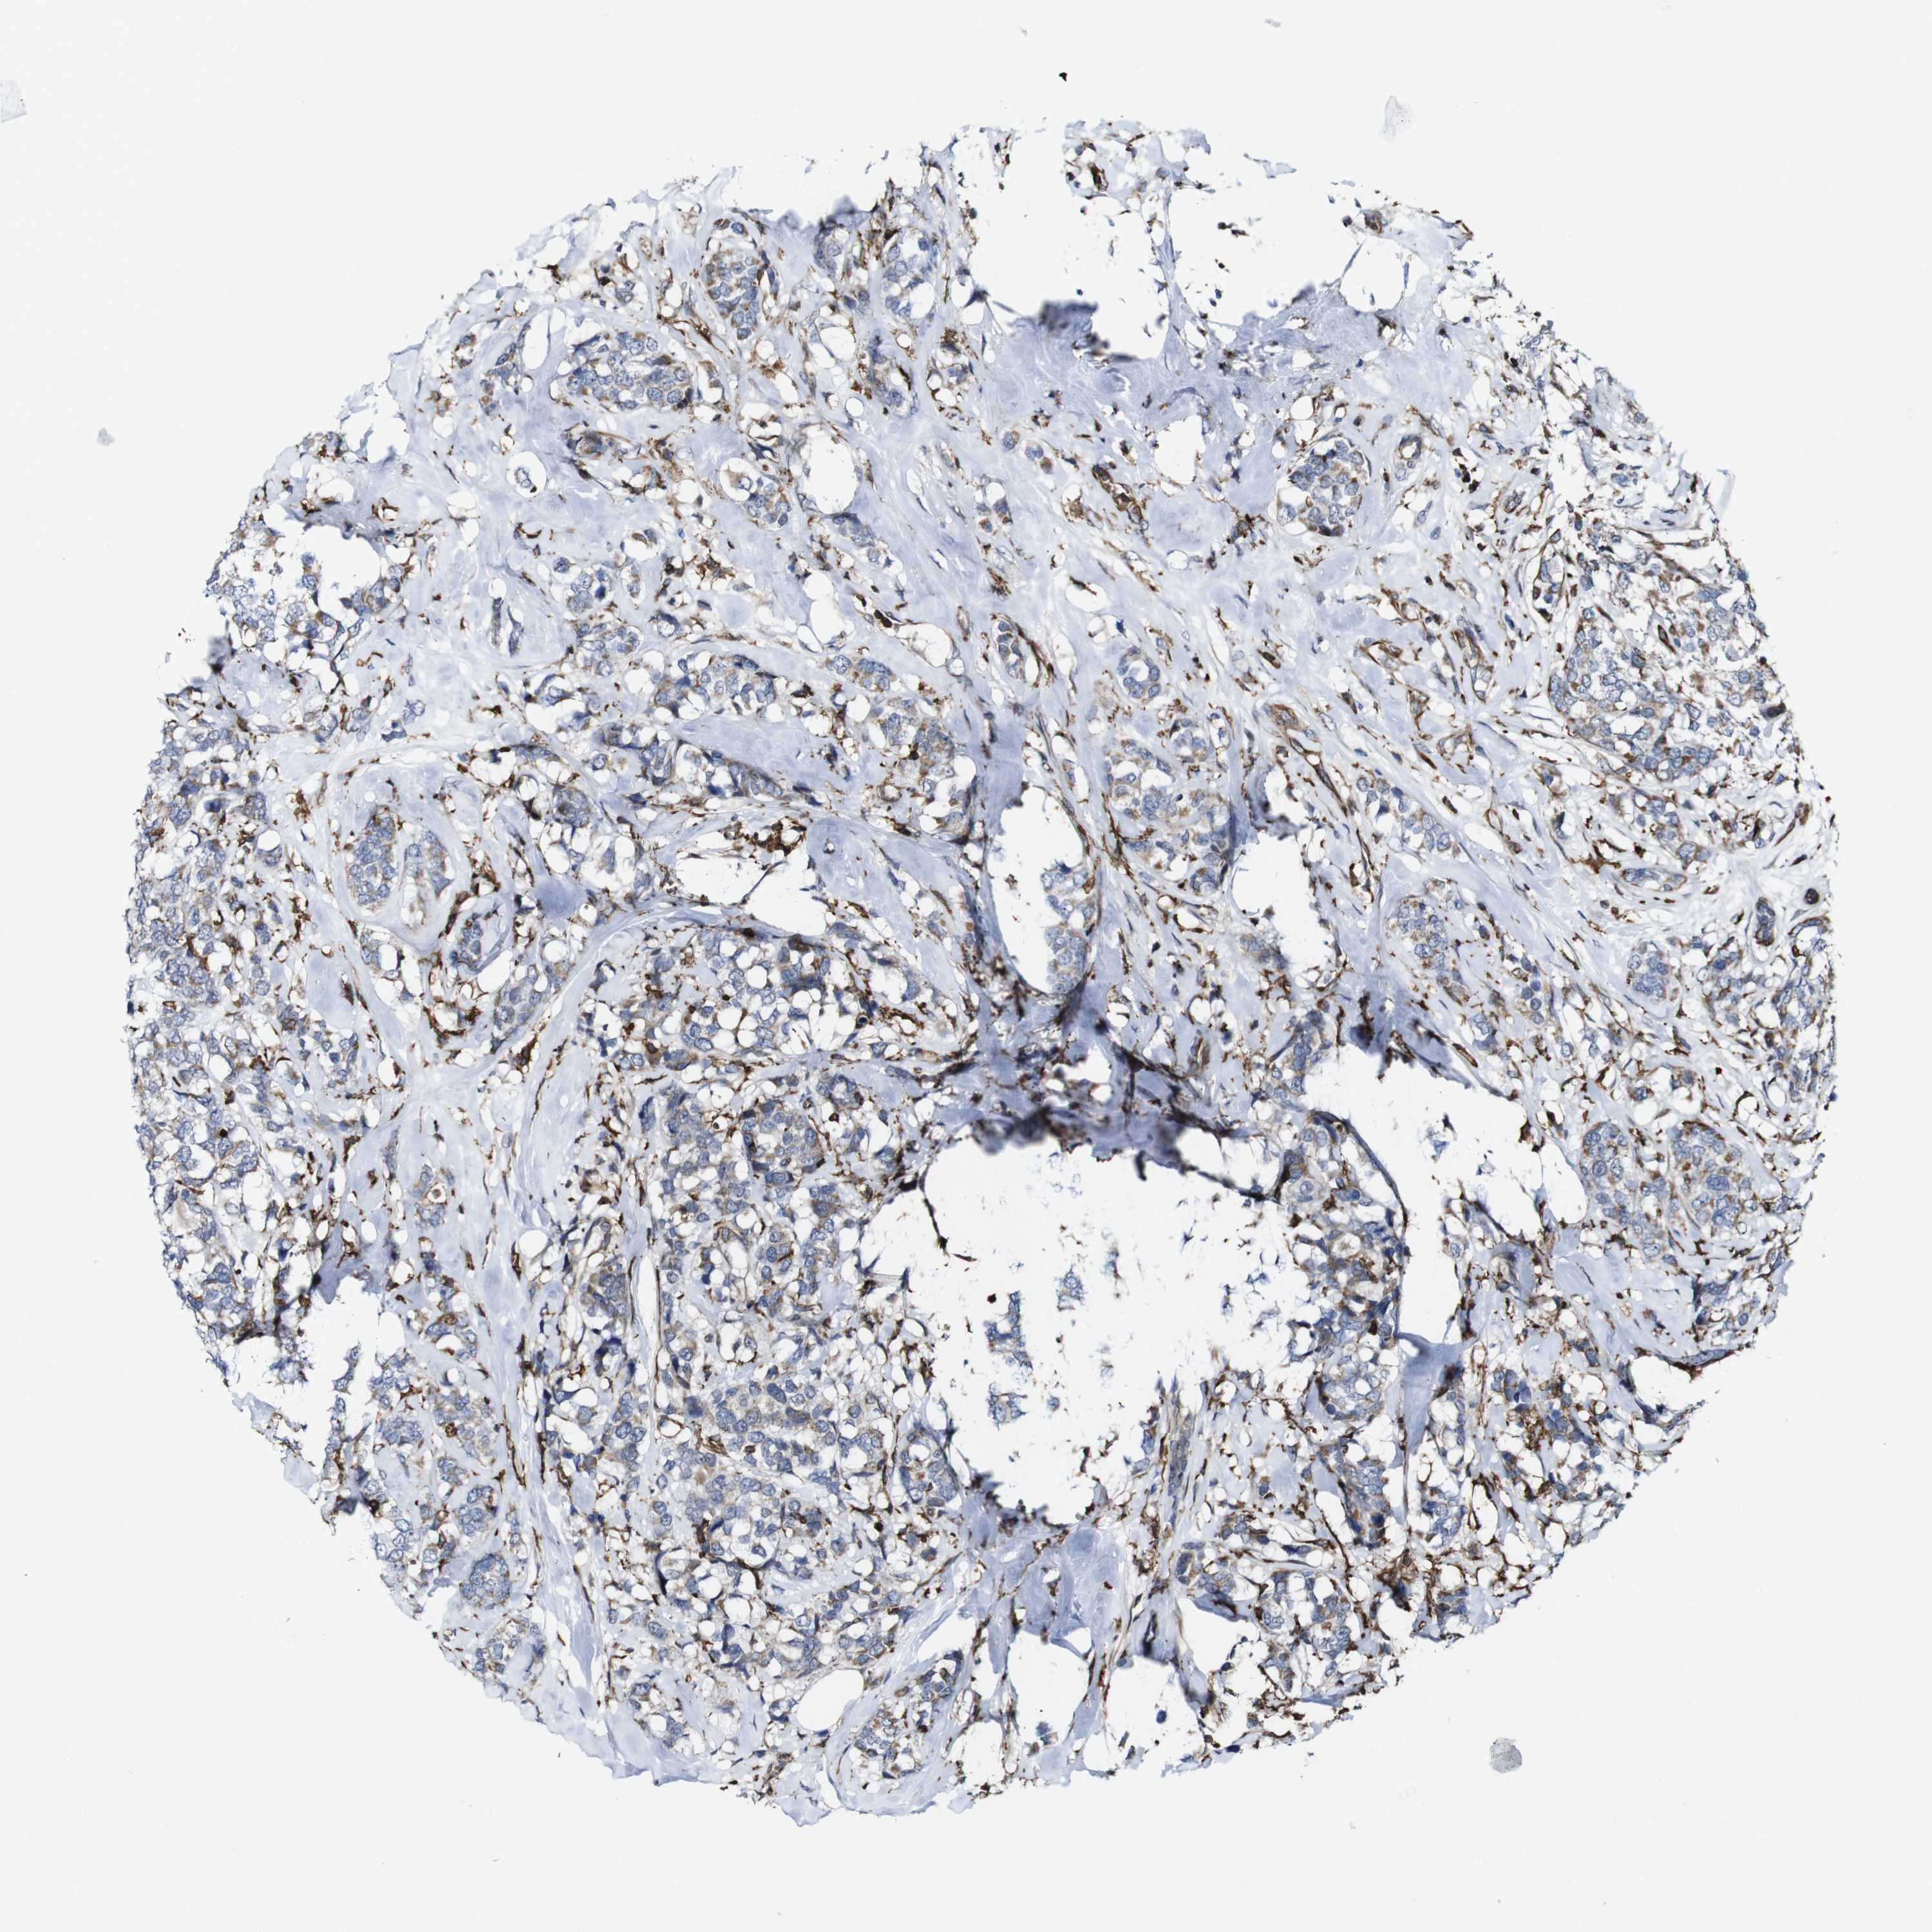

CANCER BREAST CANCER Show tissue menu

BRCA TCGA BRCA VALIDATION PROTEIN EXPRESSION

ANTIBODIES

AND

VALIDATION